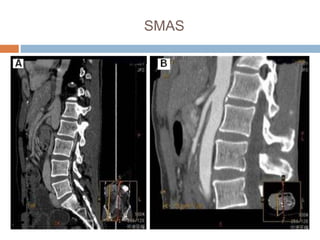

Superior mesenteric artery

syndrome (SMAS)

 Superior mesenteric artery syndrome is a rare condition first described by

Rokitansky in1861. The condition results from a reduced angle between the

artery at its origin from the abdominal aorta and the transverse third part of

the duodenum causing duodenal obstruction. Diagnosis of the syndrome

depends on high index of suspicion, augmented by the radiological features

of the syndrome. Treatment can either be conservative or operative,

depending on the severity of the condition.

Case report

 A 19-year-old female presented to the out-patient department of

King Fahad Medical City with a two-year history of recurrent

abdominal pain associated with feeling of fullness and vomiting after

meals together with progressive loss of weight (>40kg) in 2 years.

On examination, she was emaciated with a body weight of 22kg.

Her vital signs were within the normal limits. The abdominal

examination revealed a slightly distended abdomen with positive

succession splash. Laboratory investigations were normal. Barium

follow-through showed a grossly distended stomach reaching down

to the pelvis

SMAS